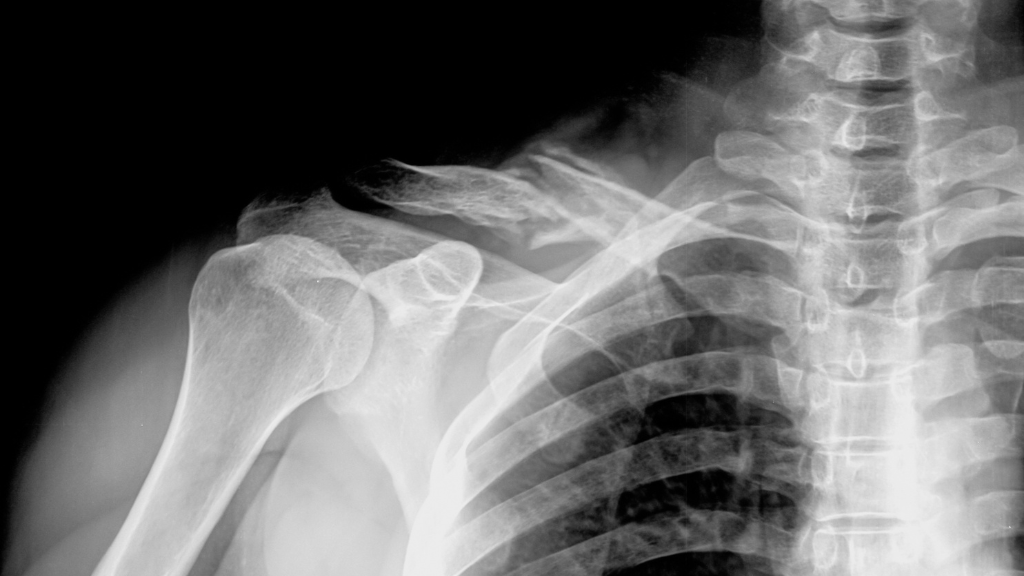

Kalzium ist entscheidend für starke Knochen. Übermäßiger Phosphorkonsum und unzureichende Calciumzufuhr führen langfristig zu einer Erweichung der Knochen. Dies erhöht das Risiko von Osteoporose und Frakturen erheblich. Insbesondere Menschen, die regelmäßig Limonade trinken, sind besonders stark betroffen.

Der menschliche Körper benötigt ein ausgeglichenes Verhältnis zwischen Kalzium und Phosphor. Wenn dieses Gleichgewicht gestört ist, holt sich der Körper das benötigte Kalzium aus den Knochen. Auf lange Sicht kann dies ernsthafte Konsequenzen für die Knochengesundheit haben. Zudem enthält Limonade keine wichtigen Nährstoffe wie Vitamine und Mineralstoffe.

Studien haben gezeigt, dass Menschen, die regelmäßig Limonade konsumieren, schwächere Knochen haben als solche, die dies nicht tun. Besonders Frauen haben ein erhöhtes Risiko für Osteoporose, wenn sie regelmäßig Cola oder andere kohlensäurehaltige Getränke konsumieren. Ein Glas hier und da ist unbedenklich, aber wer täglich Limonade trinkt, hat ein viel höheres Risiko für Knochenerkrankungen.